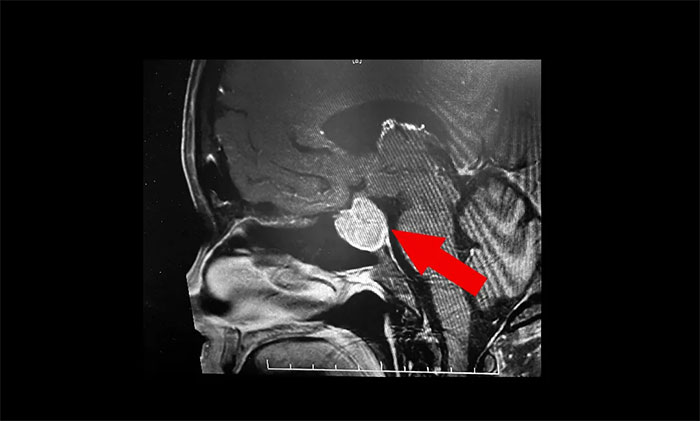

鞍區(qū)MRI平掃+增強顯示:蝶鞍顯著擴大,鞍區(qū)見不規(guī)則狀腫塊,大小超3公分。病變向鞍上生長,突入鞍上池,推移視交叉;向鞍旁生長,侵及左側(cè)海綿竇,海綿竇內(nèi)頸內(nèi)動脈包裹,繼續(xù)向側(cè)旁生長,毗鄰左側(cè)顳葉受壓內(nèi)移向后生長。

▲ 影像顯示垂體占位,侵犯海綿竇

李士其教授、潘仁龍主任、吳治群博士組成的專家組會診后,考慮為侵襲性巨大垂體腺瘤。從影像學(xué)資料上看,瘤體已經(jīng)十分巨大,占據(jù)鞍區(qū),并向蝶竇和鞍上發(fā)展,侵襲左側(cè)海綿竇,視神經(jīng)、視交叉受壓,應(yīng)立即施行手術(shù)切除,解除壓迫,若任其發(fā)展,將面臨失明的風(fēng)險。